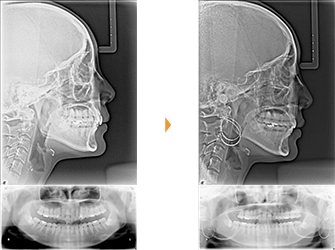

| 主訴 | 前歯が出ている |

| 年齢・性別 | 35歳 / 女性 |

| 治療方針 | 叢生も前歯の突出も大きいケース。小臼歯抜歯だけでは改善できないため、大臼歯の抜歯も行なった。 |

| 抜歯部位 | 上下顎左右小臼歯、左上第1大臼歯(計5本) |

| 使用装置 | マルチブラケット装置 |

| 治療期間 | 36か月 |

| リテーナー | 上顎インビジブル、フィックス、下顎インビジブル |

| 費用 | 885,000円(税別) |